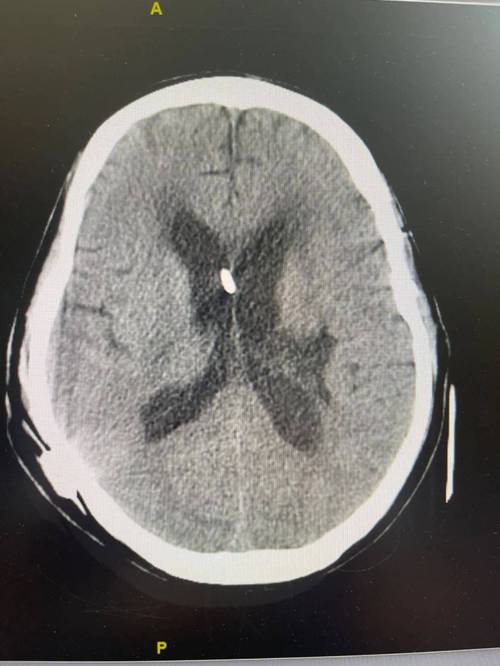

这是一个影像学(通常是CT或磁共振MRI)诊断报告,描述的是大脑中特定区域出现了多个由缺血引起的、已经坏死的脑组织。

- 解读:简单说,就是“脑梗塞”或“中风”留下的“疤痕”,这些坏死的脑组织无法再生,会形成小的腔隙,影像上看起来就是“病灶”。

在大脑两侧、靠近脑室的区域,出现了多个由于小血管堵塞或缺血导致脑组织坏死的病灶。

这种病灶在临床上有一个更常见的名称,叫做“腔隙性脑梗塞” (Lacunar Infarction)。